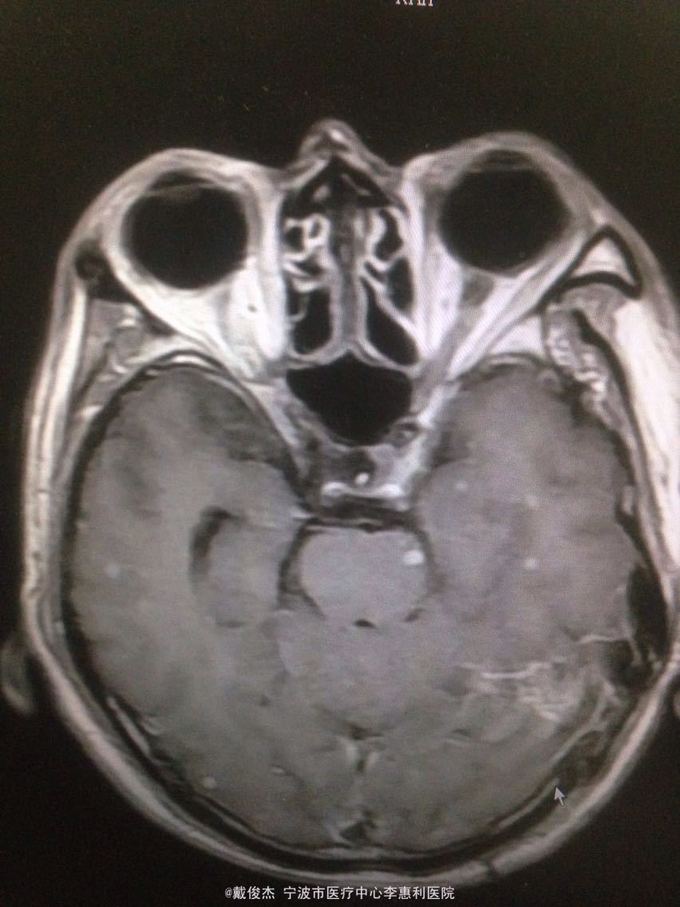

查体:神志清,双肺啰音,颅神经阴性,颈抵抗,四肢肌力正常,双巴氏征阴性 辅查:脑脊液压力380mmH2O,细胞4100/ul,多核90%,单核10%,蛋白223mg/ml。胸部CT示:两肺多发粟粒小结节。头颅MRI示:双侧大脑半球、脑干、小脑多发病灶。

诊断:结核性脑炎,肺结核 处理:抗痨治疗,激素,降颅压,保护神经和对症支持治疗